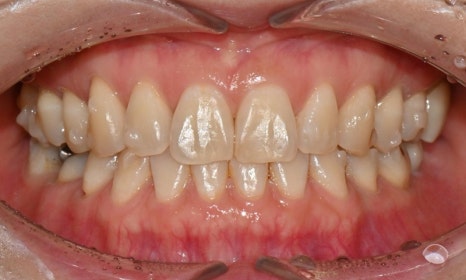

ICON 치료 전후

이러한 white spot은 미백을 하고 난 후 1~2주 정도 지나면 치아 내부의 수분이 안정화되고 미세한 재광화가 일어나면서 색대비가 자연스럽게 완화되지만, 만약 white spot에 대한 적극적인 개선을 원할 경우 미백을 한 후 최소 2주 정도 시간이 지난 후 ICON 치료(레진침투치료)를 고려할 수 있습니다.